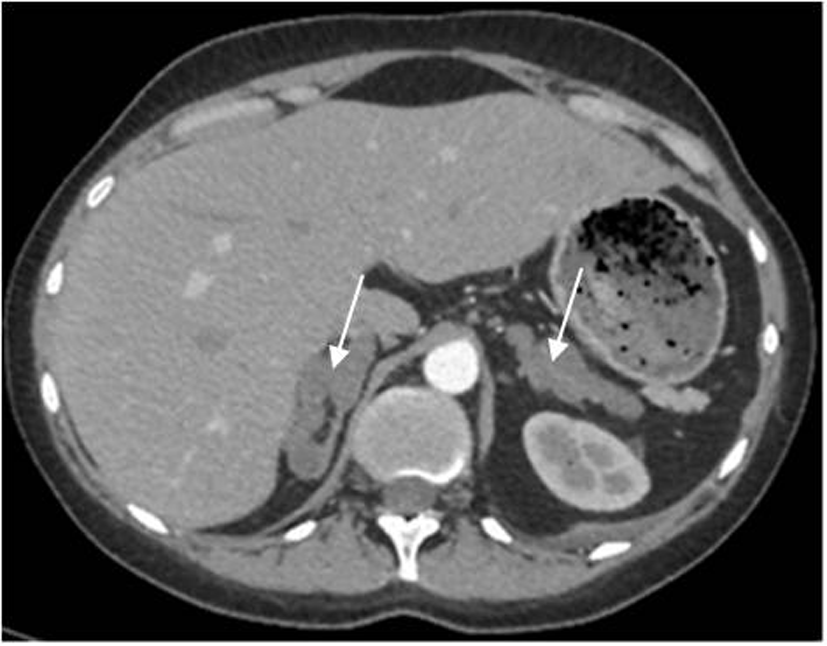

При обследовании в отделении нейроэндокринологии и остеопатий в сентябре 2016 г. у пациентки Ю. был подтвержден АКТГ-независимый эндогенный гиперкортицизм (см. таблицу). В биохимическом анализе крови: калий – 4,5 ммоль/л (3,5–5,1), глюкоза – 4,42 ммоль/л, холестерин – 7,8 ммоль/л (3,3–5,2). В суточной моче метанефрин – 194 мкг (25–312), норметанефрин – 347 мкг (35–445). По данным МСКТ: надпочечники обычно расположены, с четкими неровными контурами. Оба надпочечника деформированы, неравномерно утолщены. Структура неоднородная за счет многочисленных объемных образований округлой и овальной формы, размером от 12 до 36 мм. Наиболее крупные образования расположены в латеральной ножке левого надпочечника (до 33 мм) и в латеральной ножке правого надпочечника (до 28 и 36 мм). Контуры образований четкие, ровные. Структура однородная. Плотность их по фазам составляет: нативная фаза – артериальная фаза – венозная фаза – отсроченная фаза: 13–37–74–38 ед.Н. Размер правого надпочечника (медиальная ножка–латеральная ножка–тело): 12–20–14 мм. Размер левого надпочечника: 18–22–10 мм. Длина правого надпочечника, включая ножки и тело, – 9,3 см, левого – 8,9 см. (рис. 1, 2). При повторной МРТ головного мозга данных за микроаденому гипофиза не получено. Таким образом, был верифицирован диагноз «Синдром Иценко–Кушинга. Первичная двусторонняя макронодулярная гиперплазия надпочечников». Пациентка была консультирована хирургом, показано хирургическое лечение. Из осложнений эндогенного гиперкортицизма подтверждена артериальная гипертензия 2 степени, по поводу чего назначены лозартан, индапамид, доксазозин с достижением целевых показателей АД.

Рис. 2. МСКТ надпочечников пациентки Ю., артериальная фаза, коронарная проекция (надпочечники указаны стрелками).